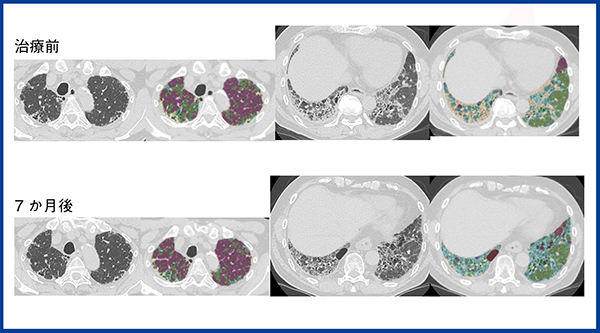

ところで,線維化も細胞浸潤も局所のCT値を上昇させるので,CT値だけでは両者を区別することはできない10)。CTで線維化を示す所見として重要なのは牽引性気管支拡張であり,牽引性気管支拡張を伴う病変は線維化を強く疑う。ただし,線維化と細胞浸潤が同時に存在する場合には,CTで牽引性気管支拡張を伴う病変であっても,ある程度ステロイド・免疫抑制剤で改善する場合がありうる。今回のQZIP-ILDでは,ラベリングの段階で,無気肺硬化型の線維化が主体のコンソリデーションは黄色,抗炎症治療である程度改善した症例のコンソリデーションをオレンジに分けて色づけした。図3に示す症例は60歳代,男性で,徐々に進行する胸部異常影で紹介となった。CTでは上葉には牽引性気管支拡張を伴うUIPパターンが認められ,高度な線維化が示唆された。下葉には気管支血管束沿いのコンソリデーションおよびすりガラス影が認められ,多彩な所見を示している。抗核抗体などもすべて陰性で,外科的肺生検でも特定の間質性肺炎と診断できず,最終的に分類不能型間質性肺炎とされた。病理組織像で下葉では細胞浸潤が目立ったことから,ステロイド・免疫抑制剤を投与したところ,下葉の病変は改善傾向にあり,呼吸機能検査も改善した。QZIP-ILDでは上葉の黄色の領域は残っているが,下葉のオレンジの領域は減少していることがわかる。QZIP-ILDで,線維化のみの病変と,線維化と細胞浸潤が混在する病変をどこまで区別できるかは,今後,さらに検討が必要と考えている。

図3 60歳代,男性,分類不能型の間質性肺炎

治療前および治療後のCTとQZIP-ILDの解析結果。治療前,呼吸機能検査では%FVC:44.2%,%DLCO:73.5%であったが,ステロイドパルス,エンドキサンパルス,その後のステロイド投与により,7か月後,%FVC:53.2%,%DLCO:86.7%まで回復した。CT画像では下葉のコンソリデーション(オレンジ)の領域は消退している。